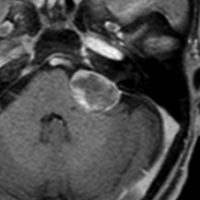

左聴力低下で発症した小脳の海綿状血管腫で,小脳橋角槽に突出するように増大しています。

左上が発症時,次が1ヶ月後,3ヶ月後,4ヶ月後と急速に大きくなったので摘出しました。

静脈奇形を伴っていませんでした。